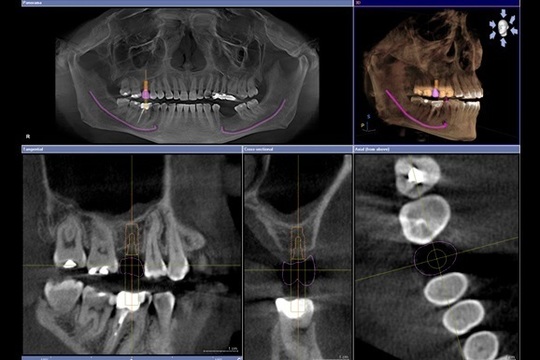

そのドイツ製システムとは、シロナ社の歯科用CT「ガリレオス」と、被せ物を自動で製作する「セレック」です。院内に専用のCTを備えることで治療前の診査・診断をより正確に行うことができ、またコンピューターでセラミックを自動で削り出すセレックを用いることで、インプラントの被せ物をより短時間で作製することができるようになっています。

それぞれの装置でデジタル化したお口の中のデータを活用し、インプラントを埋め込む位置や被せ物のシミュレーションを行えますので、より安全で自然な仕上がりのインプラント治療が可能なのです。

当院ではドイツシロナ社のセレック、歯科用CTガリレオスと連動することで院内でCTによる診査診断ができセレックによりインプラントの被せ物が作製できるようになりました。

セレックの口腔内印象をガリレオスのCTデータと重ね合わせインプラントの埋入位置の確認と被せ物のシュミレーションをします。

セレックとガリレオスのシュミレーションにより出来た外科用ガイドです。これにより最終的な被せ物の位置を考慮し外科的に安全な位置にインプラントを埋入することができます。